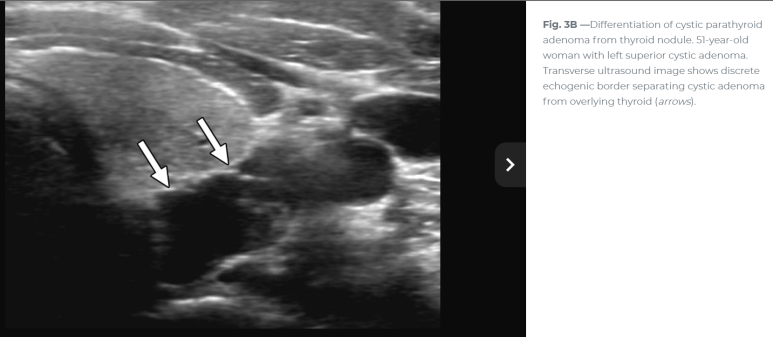

이번 사례와 같은 위치에 비슷한 모습

For nonfunctional parathyroid cysts, which are usually large simple epithelial cysts, the sonographic features are unlikely to add much specificity to the diagnosis. The primary role of ultrasound in these cases is to guide cyst aspiration for PTH assay to confirm parathyroid origin and potentially for therapeutic intervention. 비기능성 낭종일 경우 초음파의 주된 역할은 부갑상선 기원을 확인하기 위해 PTH assay를 위해 낭종 흡인을 보하는 것이다.

Ultrasonography is considered to be the first line imaging modality as part of the diagnostic workup. The sensitivity and specificity of this is operator-dependent but is likely to reveal a cystic nodule that can often be difficult to differentiate from a thyroid cyst 크기가 크면? 갑상선 낭종과 구별이 어려울때도. The absence of comet tail artefacts, which, if present, would indicate a colloid cyst, as well as the lack of other cystic lesions within the thyroid lobes may raise the suspicion of a parathyroid origin. However, differentiation of parathyroid cysts from thyroid cysts based on radiological findings is challenging.